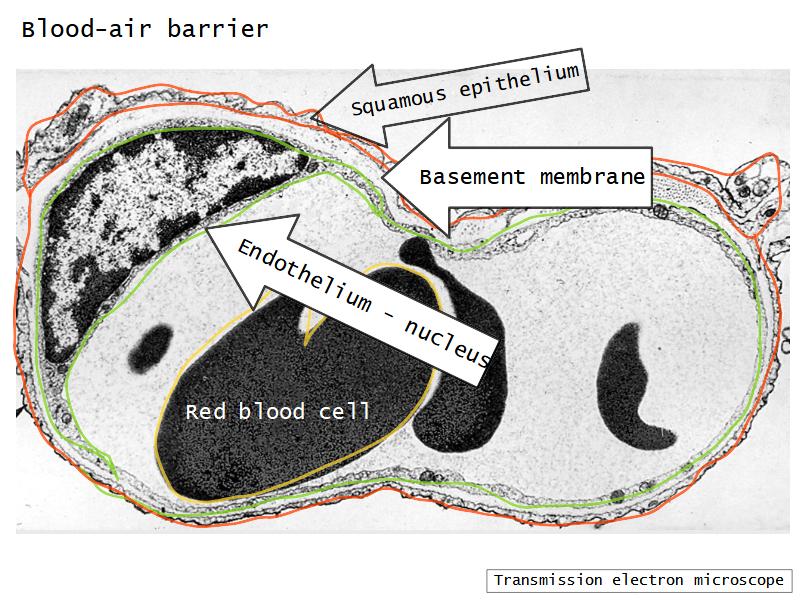

Components of the Blood-Air Barrier?

What other barrier systems are found in the body?

What are the purpose of each of these barrier systems? Connected with physiology will unlock the pathology.

Barriers

- Skin

- Blood-air

- Blood-brain

- Blood-retina

- Blood-thymus

- Blood-testis

- Placental barrier